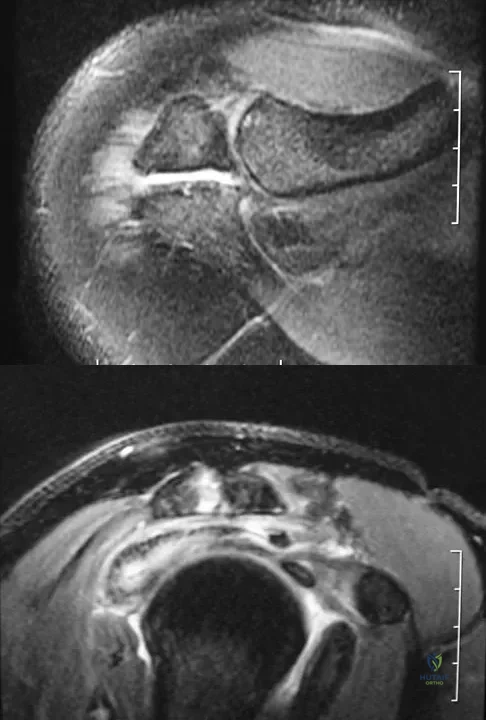

A 52-year-old woman reports nagging shoulder pain that has been present for months and is slowly progressive in nature. The patient also reports nocturnal pain and notes that the pain is not activity related. Figures 27a and 27b show the radiograph and bone scan, and Figures 27c through 27e show T1-weighted, T2-weighted, and gadolinium MRI scans, respectively. Based on these findings, what is the most likely diagnosis?

The radiograph reveals a metaphyseal lesion with some stippled mineralization suggesting a chondroid tumor. The bone scan shows increased uptake, beyond what is expected for a simple enchondroma, and beyond the limits of the lesion. The MRI sequences shows a lobular lesion on the T1- and T2-weighted (bright on the T2 sequence) images with inhomogeneous uptake of gadolinium; both findings are typical for a chondroid lesion. The history of pain, the positive bone scan, the age of the patient, the size of the lesion, and the central location (enostotic) of the lesion all suggest a malignant cartilage tumor. The images are not consistent with the other diagnoses. In particular, plasmacytoma is more uniformly bright on T2-weighted images and often has a negative bone scan. Menendez LR (ed): Orthopaedic Knowledge Update: Musculoskeletal Tumors. Rosemont, IL, American Academy of Orthopaedic Surgeons, 2002, pp 187-194.